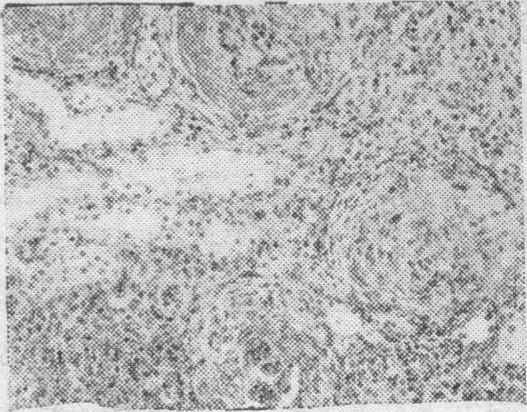

病肾的急性期病变主要为增殖性肾炎,伴有蛋白质渗出(图1)。数周后肾小球内新月体形成(图2),逐渐发展为整个小球纤维化及玻璃样变(图3)。电镜检查肾小球基膜增厚、破裂,沿肾小球基膜内皮细胞下有电子致密物沉积(图4)。免疫荧光检查肾小球及部分肾小管基膜上有免疫球蛋白(在第一阶段只有异体的,第二阶段又加上自体的)及补体,有时还有纤维蛋白原呈均匀的线条状沉积。

图1肾小球肿胀,内皮细胞及系膜细胞增生(H. E.×500)